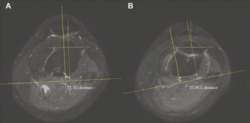

소아청소년 슬개골 탈구 위험 예측 지표가 제시됐다. 수술 여부 판단과 정확한 교정을 위한 지표로 활용될 수 있을 것으로 기대를 모은다.분당서울대병원 정형외과 성기혁 교수팀은 최근 20세 이하 소아청소년 596명의 무릎 MRI 영상을 통해 슬개골 불안정성 위험을 예측하는 기준값을 알아보기 위한 연구를 진행했다.성인의 경우 경골결절과 활차구 사이(TT-TG) 및 경골결절과 후방십자인대 사이(TT-PCL) 거리로 불균형 여부를 판단하고, 슬개골을 제자리로 되돌리는 ‘원위부 재정렬 수술’을 시행한다.그동안 슬개골 불안정성이 성인보다 스포츠…